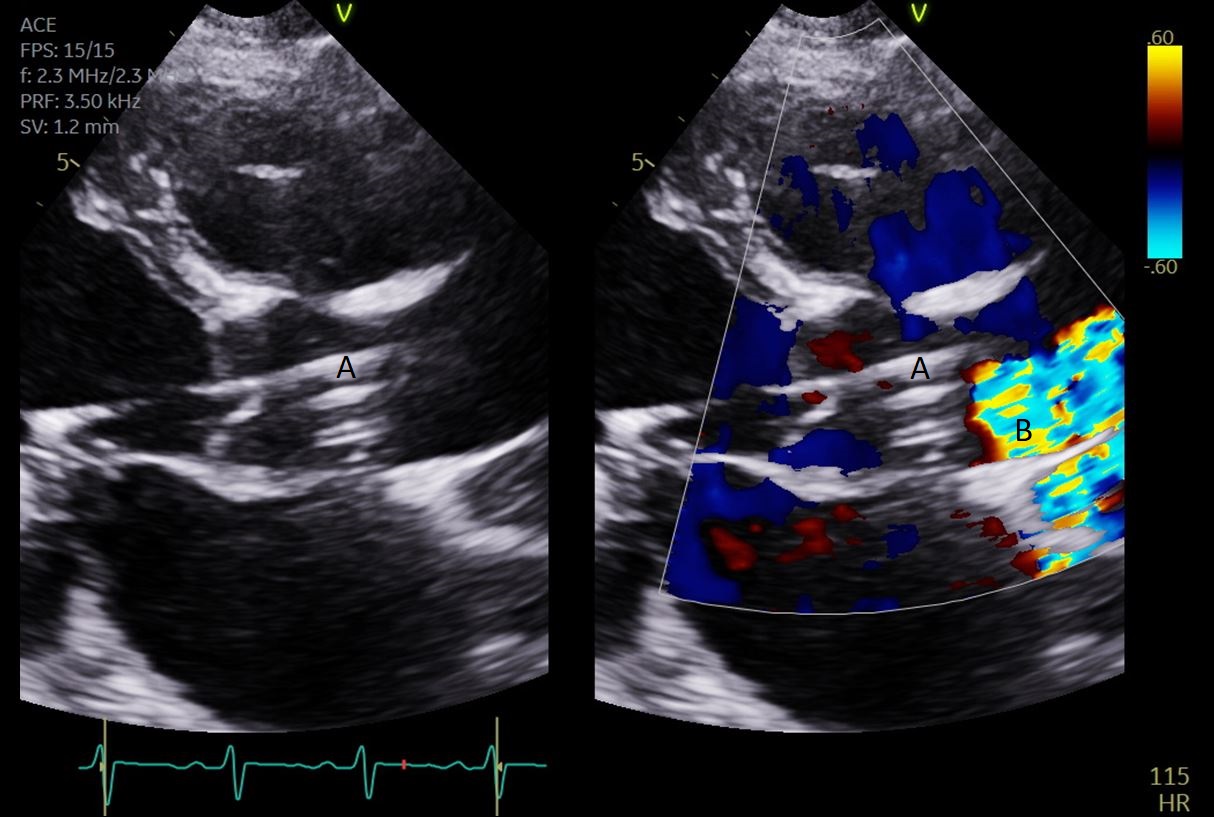

Impella (A) in the LV cavity caused disruption and damage to subvalvular apparatus resulting in flail segment (B) of the mitral valve.

Fig. 4.Impella (A) placement causing disruption and damage to subvalvular apparatus resulting in mitral valve flail (B) and mitral regurgitation (C).